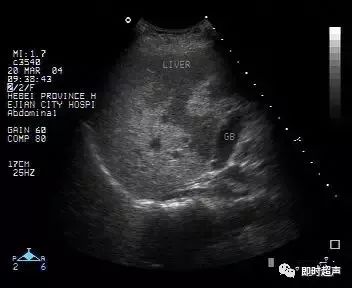

超声表现:

1、肝实质回声细密增强,呈云雾状,后方回声衰减。

2、肝内管道结构显示欠清。

3、肝肾对比阳性,正常情况下肝脏回声略高于肾实质回声,脂肪肝时肝脏回声明显增强。

4、肝脏增大,形态饱满,边缘变钝。

非均匀性脂肪肝:脂肪肝形成和发展过程中,受到门静脉血流中胰岛素和胰高血糖素含量以及肝内门静脉-体腔静脉交通支等因素的影响,脂肪浸润可表现为非均匀性。

依据超声表现可分为四型:

1、局灶浸润型:呈局灶性强回声,无包膜,边界不清,后方可伴衰减。

此型需与肝转移癌及肝血管瘤鉴别。

2、多灶浸润型:在回声相对正常的肝内,可见多发强回声。

3、叶段浸润型:一部分区域为低回声,其它区域为强回声。

此型需与肝转移癌鉴别,此型肝内血管走行正常,无靶环征及牛眼征。

4、正常肝残留型:肝脏弥漫性回声增强,其内可见低回声区,为轻度脂肪浸润或性对正常肝残留区,好发于胆囊床、门静脉主干周围。